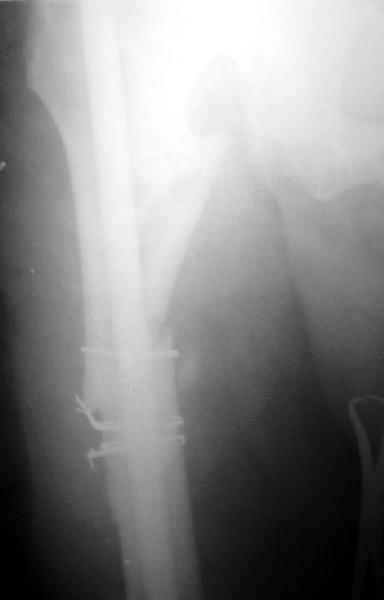

1) Мы бы не убирали проволоку, и вообще не вмешивались открыто на очаге - это ничего не даст, кроме ухудшения кровоснабжения концов отломков. Если просто закрыто перештифтовать при подобной картине, лучше с рассврливанием - это по нашему опыту дает сращение в 100%. В приложении пример - болезненное несращение более года, результат через полгода.

1